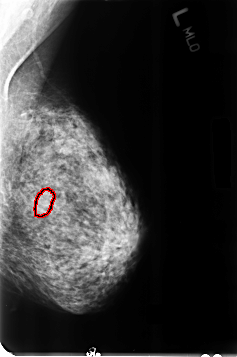

FILE: B_3357_1.LEFT_MLO.OVERLAY

TOTAL_ABNORMALITIES 1

ABNORMALITY 1

LESION_TYPE MASS SHAPE OVAL MARGINS CIRCUMSCRIBED-OBSCURED

ASSESSMENT 4

SUBTLETY 2

PATHOLOGY BENIGN

TOTAL_OUTLINES 1

BOUNDARY